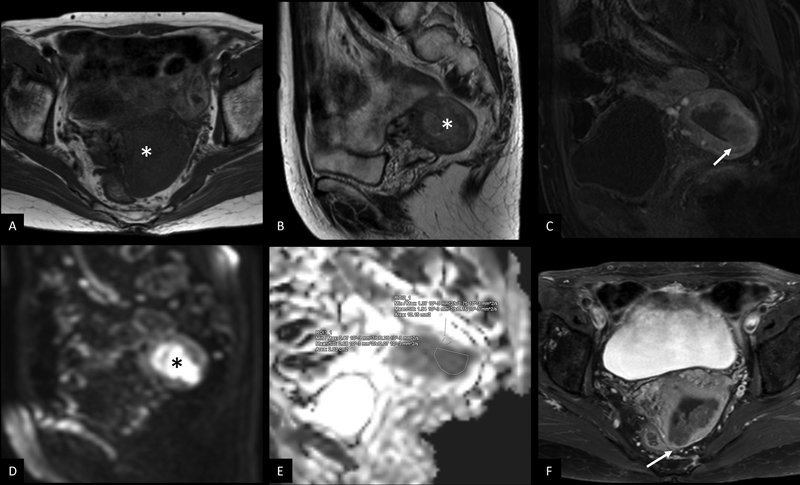

Dynamic contrast-enhanced MRI ([Fig. 4]) is the preferred imaging modality to evaluate myometrial invasion with high accuracy (59% to 100%), sensitivity (71%- to 100%), and specificity (72%-to 100%).[23] The staging accuracy ranges from 83%-to 92%.[24] [25]

| Figure 4:Dynamic contrast-enhanced MRI pelvis in carcinoma endometrium (stage IB). T1 axial oblique (A) and T2 sagittal (B) show an ill-defined polypoidal mass lesion (*) in the endometrial cavity. DCE MRI (C) shows mild contrast enhancement of tumor and disruption of subendometrial zone of enhancement (arrow in C) with myometrial invasion of >50%. DWI (D) shows diffusion restriction (*) with low ADC value in the ADC map (E). Post contrast T1 axial oblique (F) shows myometrial invasion of >50%-with intact serosal margin (arrow in F).

| Figure 4:Dynamic contrast-enhanced MRI pelvis in carcinoma endometrium (stage IB). T1 axial oblique (A) and T2 sagittal (B) show an ill-defined polypoidal mass lesion (*) in the endometrial cavity. DCE MRI (C) shows mild contrast enhancement of tumor and disruption of subendometrial zone of enhancement (arrow in C) with myometrial invasion of >50%. DWI (D) shows diffusion restriction (*) with low ADC value in the ADC map (E). Post contrast T1 axial oblique (F) shows myometrial invasion of >50% with intact serosal margin (arrow in F).